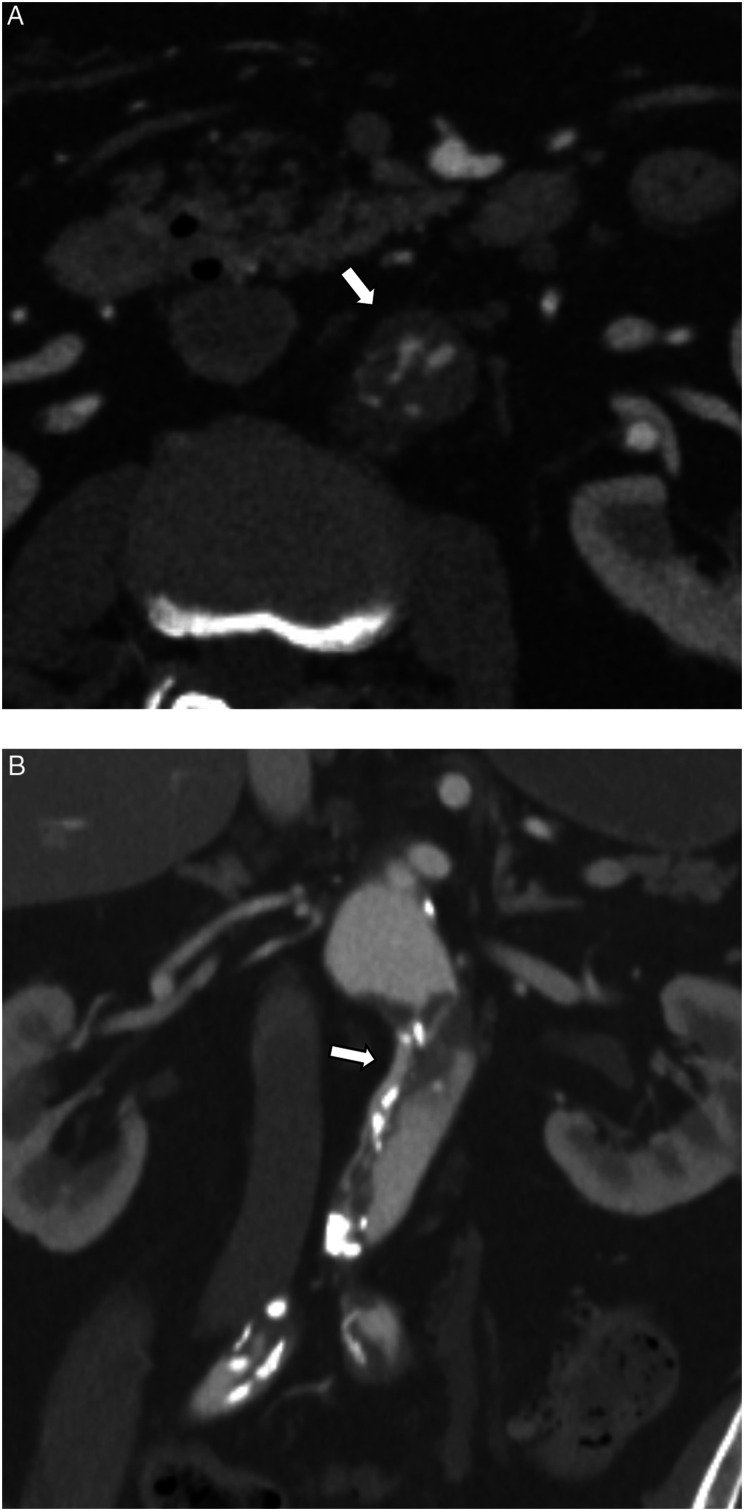

我们报告一例复杂的孤立性肾下腹主动脉夹层(IAAD)用支架移植治疗。一名79岁男性,表现为急性双侧下肢疼痛。2小时后行CT增强检查,发现IAAD所致严重的腹下主动脉狭窄。血管造影发现在IAAD上端下方有原发性撕裂。在远端放置一个较小的支架以避免支架诱导的新进入,在近端放置一个较大的支架以覆盖原进入。手术后狭窄立即改善,疼痛得到缓解。对于IAAD来说,放置支架关闭入口似乎是一种有效的方法。

We report a case of complicated isolated infrarenal abdominal aortic dissection (IAAD) that was treated with stent graft. A 79-year-old man presented with acute bilateral lower limb pain. A contrast-enhanced CT performed 2 h later revealed sever stenosis of infrarenal abdominal aorta due to IAAD. Angiography identified a primary tear just below the upper end of the IAAD. A smaller stent graft was placed distally to avoid stent graft-induced new entry, and a large stent graft was placed proximally to cover the primary entry. The stenosis improved immediately after the procedure, and pain relief was achieved. Stent graft placement for entry closure appeared to be an effective for IAAD.